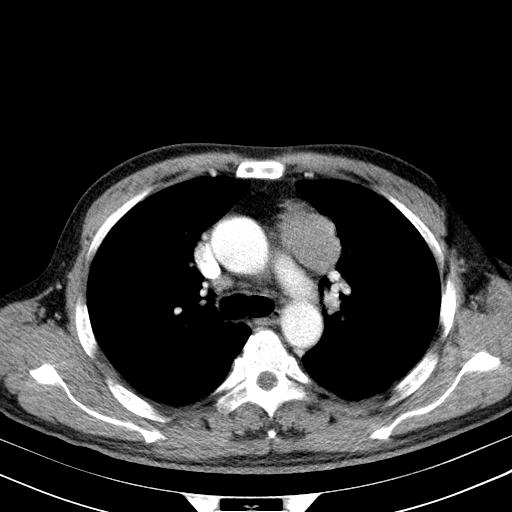

淋巴瘤?胸腺瘤?

支持淋巴瘤

淋巴瘤可能

1)考虑淋巴瘤。2)双侧少量胸腔积液。

淋巴瘤